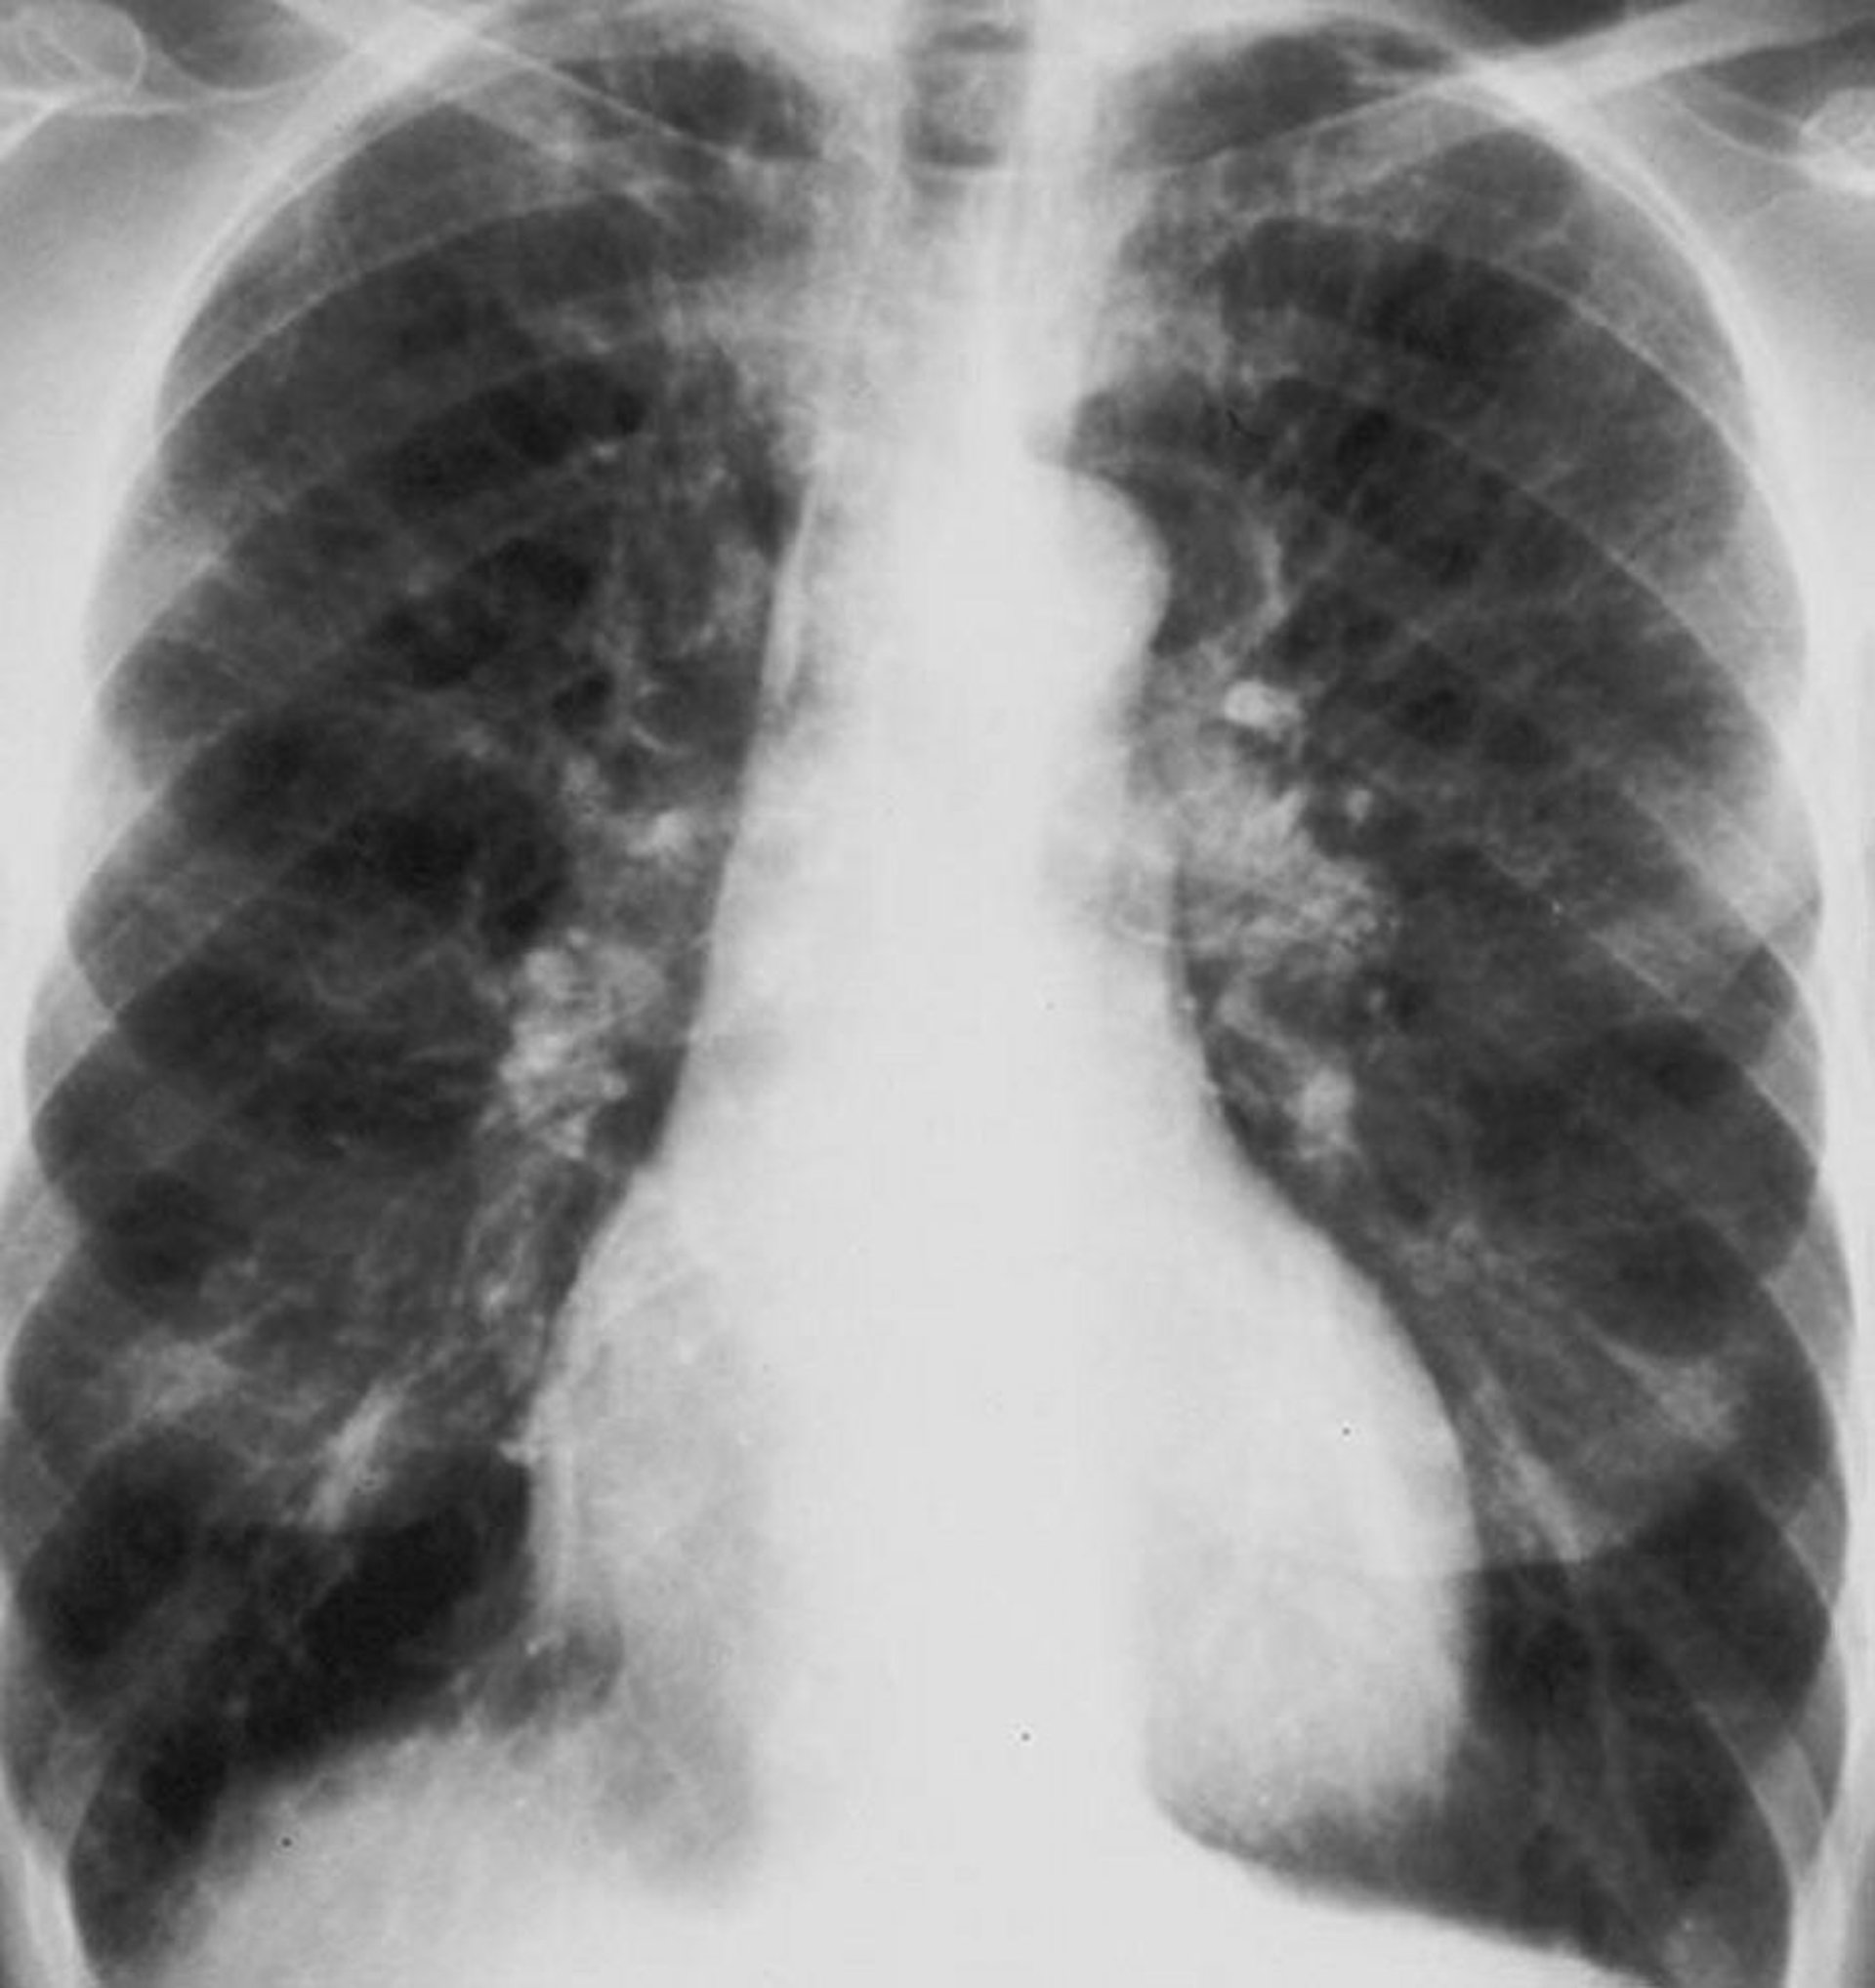

Bronchopneumopathie chronique obstructive (BPCO) (radiographie du thorax)

Radiographie thoracique d'un patient atteint de bronchopneumopathie chronique obstructive (BPCO). Les poumons sont en hyperinflation, le diaphragme est aplati, les lignes vasculaires sont augmentées et la dimension du cœur est légèrement augmentée.

By permission of the publisher. From Barnes P. In Bone's Atlas of Pulmonary and Critical Care Medicine. Edited by J Crapo. Philadelphia, Current Medicine, 2005.